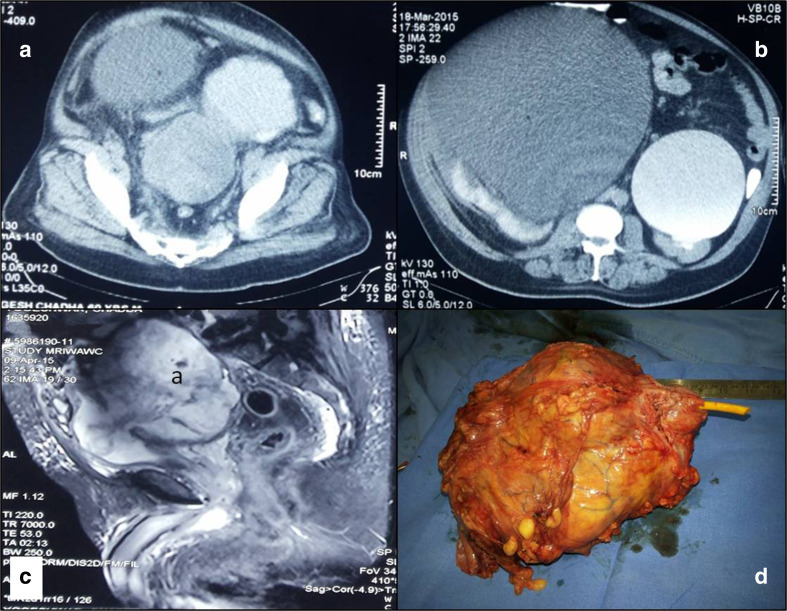

Subsequent CT and MRI revealed bilateral gross hydroureteronephrosis. Excretory phase of CT urogram showed multiple bladder diverticulae and anterior displacement of the bladder by a heterogenously enhancing and irregular nodular intravesical mass arising from one of the posteriorly located bladder diverticulum, Fig. 1. The mass was causing extrinsic compression of both the distal ureters and sigmoid colon but with preserved fat planes. Prostate and bilateral seminal vesical seemed normal on MRI, Fig. 1. Urine cytology was negative. Rigid cystourethroscopy was not successful due to elongated and anteriorly displaced posterior urethra. Flexible cystoscopy with biopsy was performed which revealed large solid tumor arising from the posterior and right lateral wall bladder diverticulum. Biopsy from lesion showed inflammatory and necrotic cells with occasional spindle cell with features of low-grade, noninvasive transitional cell carcinoma, (papillary architecture without lamina propria invasion with focal loss of polarity). PET CT showed no abnormal uptake other than the tumor.

Contrast-enhanced computerized tomography showing diverticular bladder with a large heterogenous mass arising in the diverticulum with bilateral gross hydroureteronephrosis (a, b), T2 weighted sequences in magnetic resonance imaging showing diverticular mass with normal prostate (c), and gross specimen of cystoprostatectomy (d)

Grossly tumor was large polypoidal mass arising from large posterior bladder wall diverticulum and replacing almost whole of the bladder measuring 150 × 130 × 110 mm, Fig. 1.